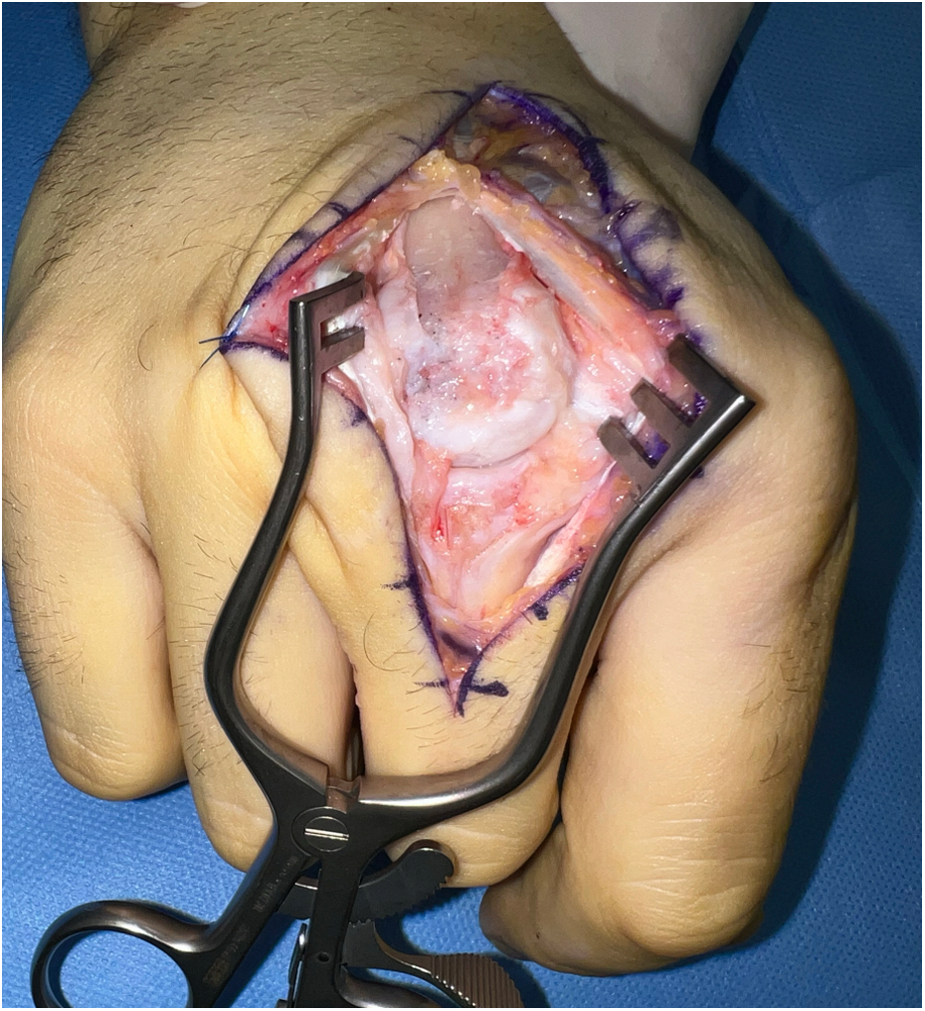

In our third case a 23-year-old male sustained a dorsal impression fracture of the third metacarpal head when attempting to strike a boxing ball in a festival machine (Figure 8). Due to his young age and physically demanding job on a building site, the patients’ main concern was pain and future osteoarthritis. Initial treatment was non-operative, with a subsequent improvement in active range of motion as swelling subsided. However, a painful clicking sensation emerged during joint movement. MRI confirmed intact base cartilage of the proximal phalanx. Considering these findings, a decision was made to reconstruct the metacarpal head using a contralateral free vascularized costochondral graft. The defect was visualized during the operation (Figure 9), after which, the graft was anchored to the remaining metacarpal using one-and-a-half millimeter cortical screws (Figure 10), with a microsurgical anastomosis linking the lateral intercostal artery to the second dorsal intermetacarpal artery, both of similar caliber. Postoperative management included initial cast immobilization, transitioning to a relative motion splint after two weeks. During the first phase of rehabilitation, a slight clicking of the joint occurred, which also disappeared spontaneously after further mobilization under guidance of the occupational therapists. Range of motion and strength is satisfactory (Figures 11 and 12), but due to his age the patient decided to pursue further education with the goal of obtaining a less physically demanding occupation in the future.

Figure 10. Case 3 intraoperative visualization of the reconstructed chondral surface of the third metacarpal head.